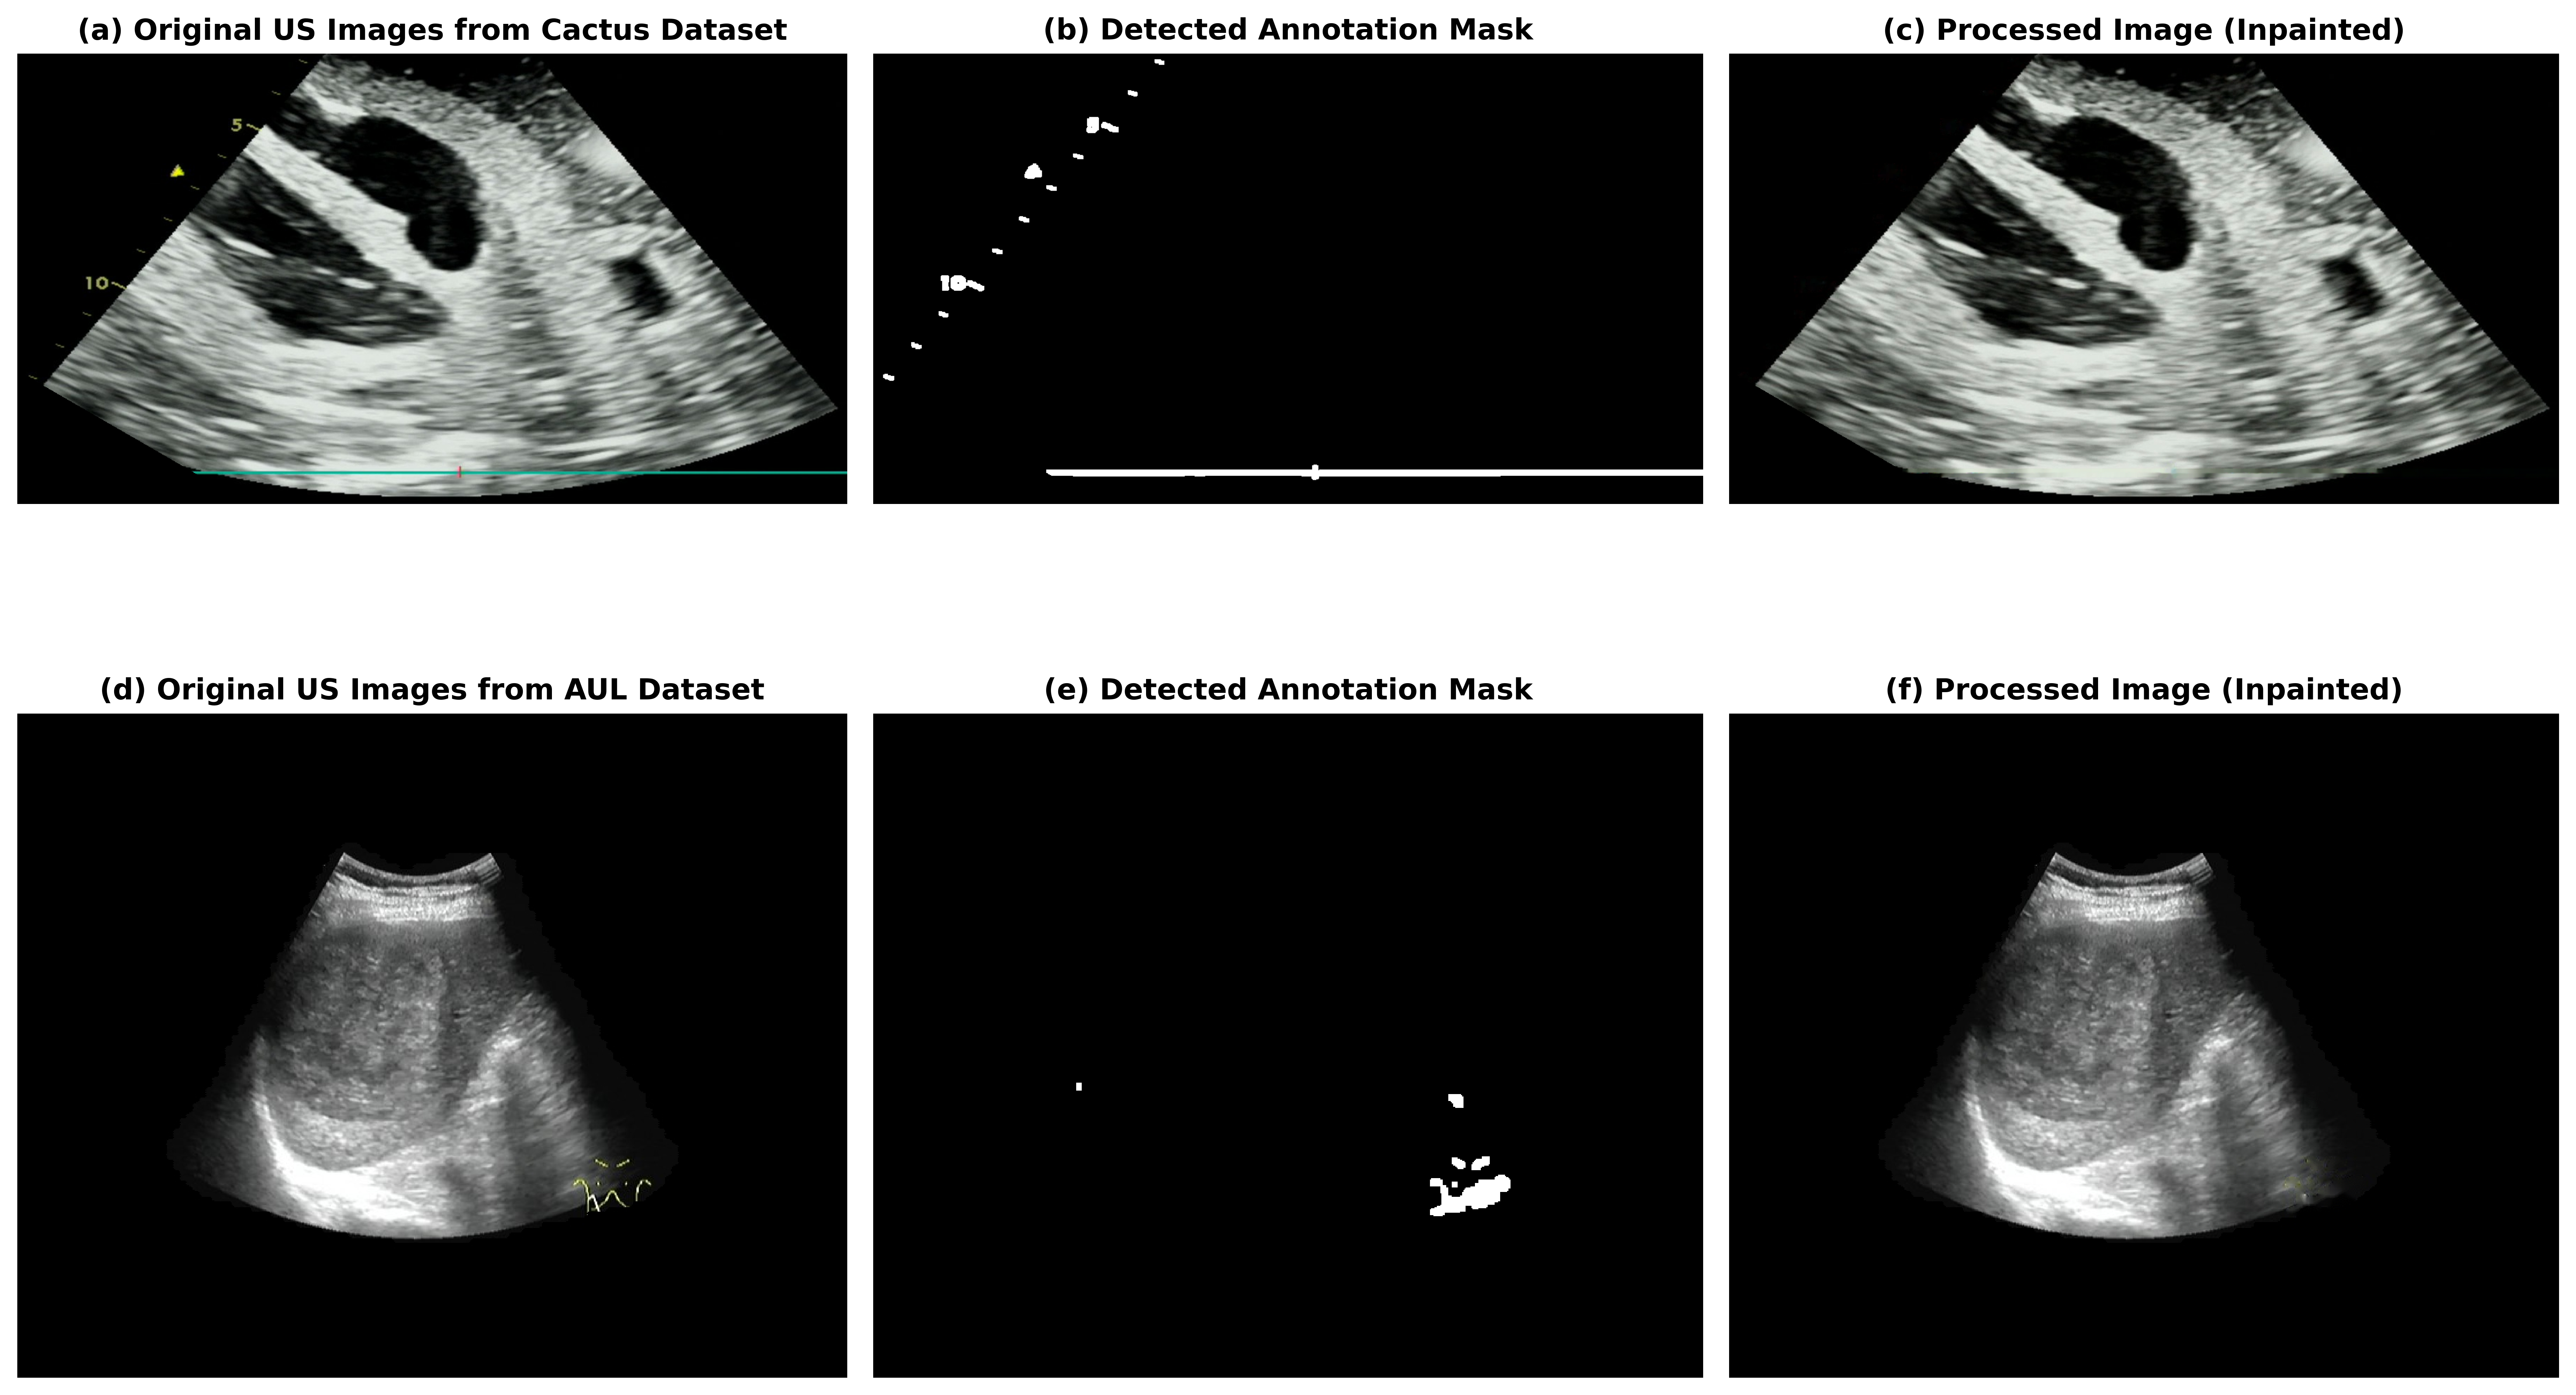

As a first step, these annotations were removed because many datasets contain overlaid text or graphical markers, such as labels, arrows, lesion outlines, and measurements, shown in Fig. 2. We implemented a unified detection and inpainting framework to automatically identify and suppress these annotations. Text elements were localized in grayscale images using Tesseract OCR (Optical Character Recognition), and bounding boxes were converted into binary masks. To detect weak or low-contrast annotations, contrast-limited adaptive histogram equalization (CLAHE) was applied to the luminance channel of the CIELAB colour space to improve visibility before detection. Colour-based annotations (including highlighter strokes and ink) were segmented in the HSV colour space, with Fig. 2C showing a 3D visualization of pixel distribution in HSV space, and highly saturated pixels are clustered using K-Means clustering. Grayscale annotations (such as pencil marks and underlines) were separated using Canny edge detection, followed by contour extraction. Masks generated from the text, colour, and grayscale channels were combined into a unified annotation mask, which was then refined using morphological closing and opening operations. Finally, a Navier-Stokes-based [67] inpainting algorithm (implemented in OpenCV) was applied to reconstruct the background structure within the masked region. This procedure effectively removed diverse annotation types while preserving underlying US information (Fig. 3 - example of annotation removal).

Refer to caption

Figure 3: US image preprocessing pipelines used for annotation removal and standardization. (a-c) Cactus dataset workflow: original US image, automatically detected colored annotation mask, and the corresponding inpainted (cleaned) image using the Navier-Stokes algorithm [67]. (d-f) AUL dataset workflow: original US image, detected annotation mask using CLAHE-enhanced K-means clustering, and the inpainted result.